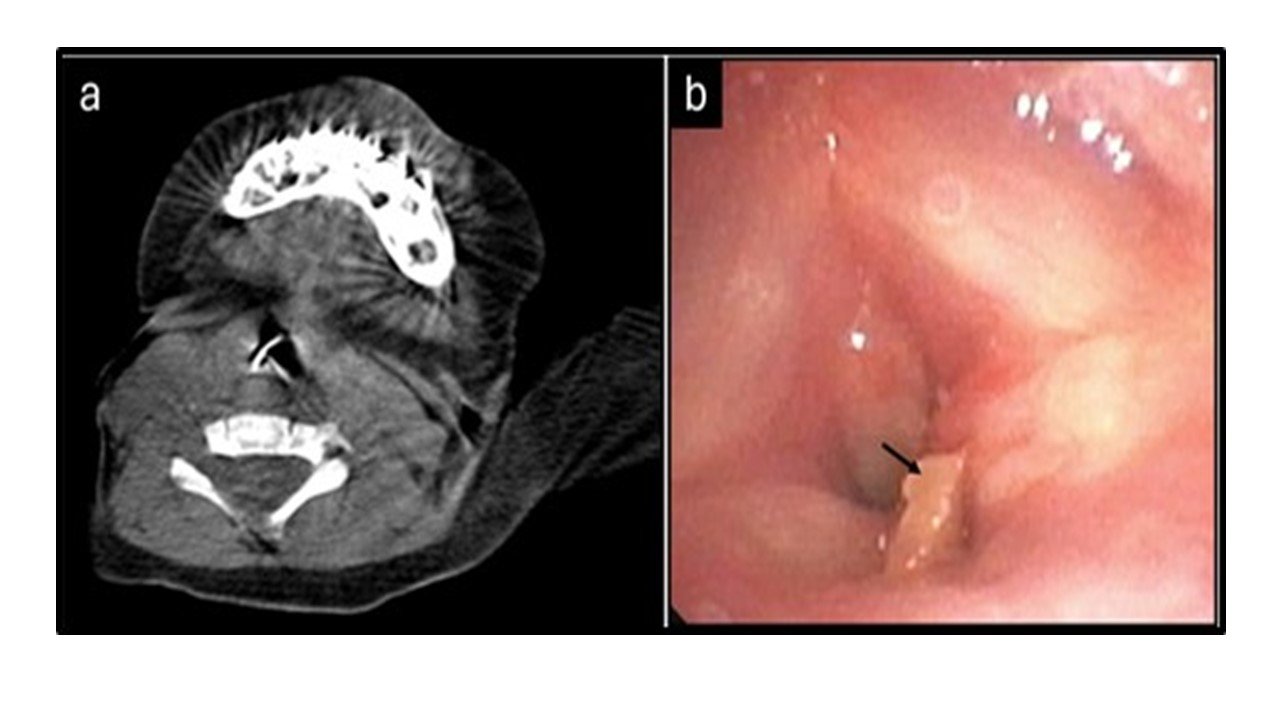

An 11-month-old infant was rushed to the emergency room with complaints of altered sensorium, labored breathing, and audible stridor. The infant had a history of hospital admission at a primary care center over the previous four days with similar complaints, for which she had received supportive care. Detailed history revealed that she had been fed chicken broth a week earlier on a festive occasion. Computed tomography of the chest showed collapse of the left upper lobe and a radio-opaque, irregular opacity suspicious of a FB in the subglottic location (Figure 1A). Diagnostic flexible bronchoscopy using a ultrathin flexible bronchoscope (Olympus BF-XP190, outer diameter 2.8 mm) under conscious sedation confirmed a large obstructing FB immediately below the vocal cords with extension to the vocal cords causing luminal obstruction (Figure 1B).

Chest CT showing a radio-opaque foreign body in the subglottic region, and flexible bronchoscopy view of the object below the vocal cords

Figure 1. A - Computed tomography (CT) of the chest showing a radio-opaque, irregular opacity suspicious of a foreign object in the subglottic location. B - Flexible bronchoscopy showing the foreign body (arrow) immediately below the vocal cords with extension to the vocal cords.